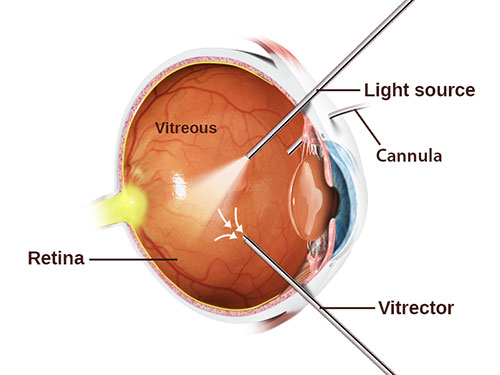

For this purpose, special methods of so-called vitreoretinal surgery are used. Its essence lies in the fact that through point punctures with long and thin instruments the surgeon enters the eye and removes cords, freeing the retina and straightening it. The process itself is very similar to the painstaking work of the master, who collects a model of a XVIII century sailboat inside the bottle through the neck of the bottle with long tweezers and scissors.

为此,使用所谓的玻璃体视网膜手术的特殊方法。 其本质在于以下事实:外科医生通过细长的器械进行点刺穿刺,使外科医生进入眼内并去除了脐带,从而使视网膜游离并变直。 这个过程本身与船长的艰苦工作非常相似,船长用长镊子和剪刀通过瓶子的颈部收集了十八世纪帆船的模型。

This operation is very thin and complex, if you remember that the retina is extremely delicate and fragile nerve tissue, and almost every part of it is responsible for any part of the vision. During the operation, the doctor looks inside the eye through his anterior segment, peeks «through the pupil.» This requires a high transparency of the optical media, that is, the cornea lens and lens should be as transparent as possible. If the lens is cloudy, that is, the patient has a cataract, then, as a rule, at the initial stage, the lens is replaced with an artificial one, and only then proceed to «repair» the retina.

The operation is performed in the “dark room”, that is, only the light guide in the surgeon’s hand or the additional light source “chandelier” lights up the working field as a chandelier, the light of the microscope is turned off.

该操作在“暗室”中进行,即,只有手术医生手中的光导或附加光源“枝形吊灯”作为枝形吊灯照亮工作区域,显微镜的光才会关闭。